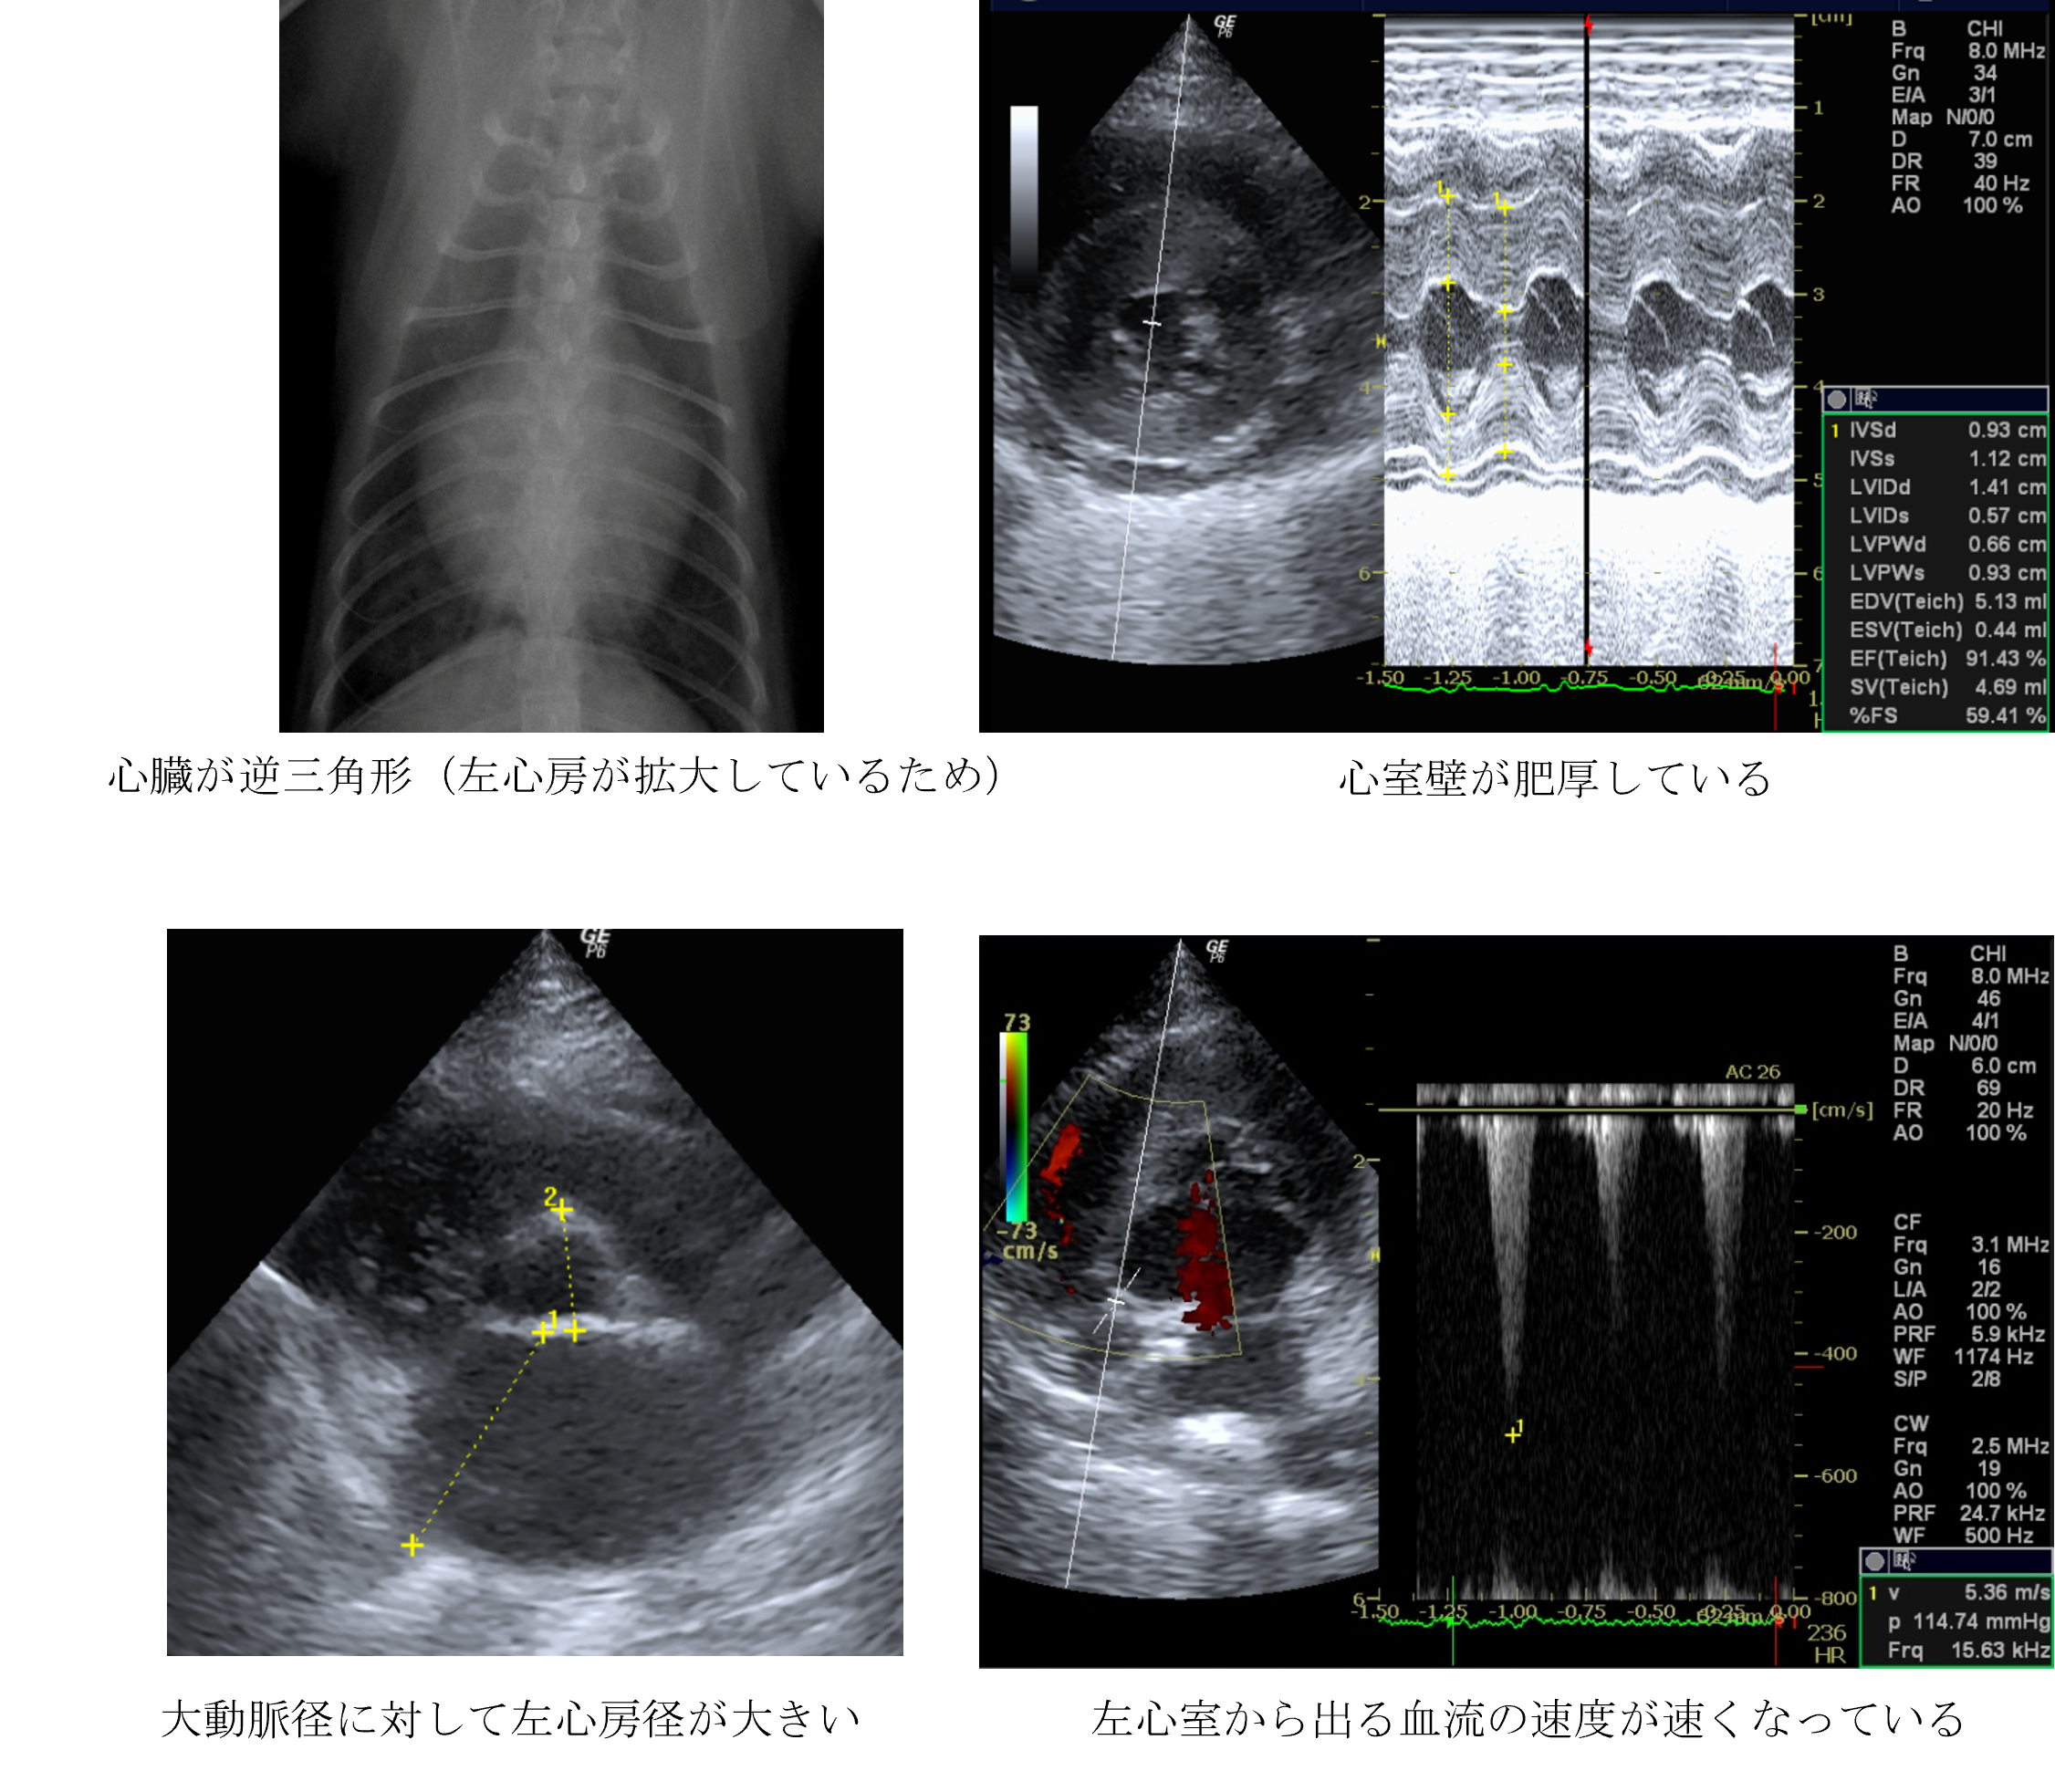

各種検査より、肥大型心筋症と診断しました。